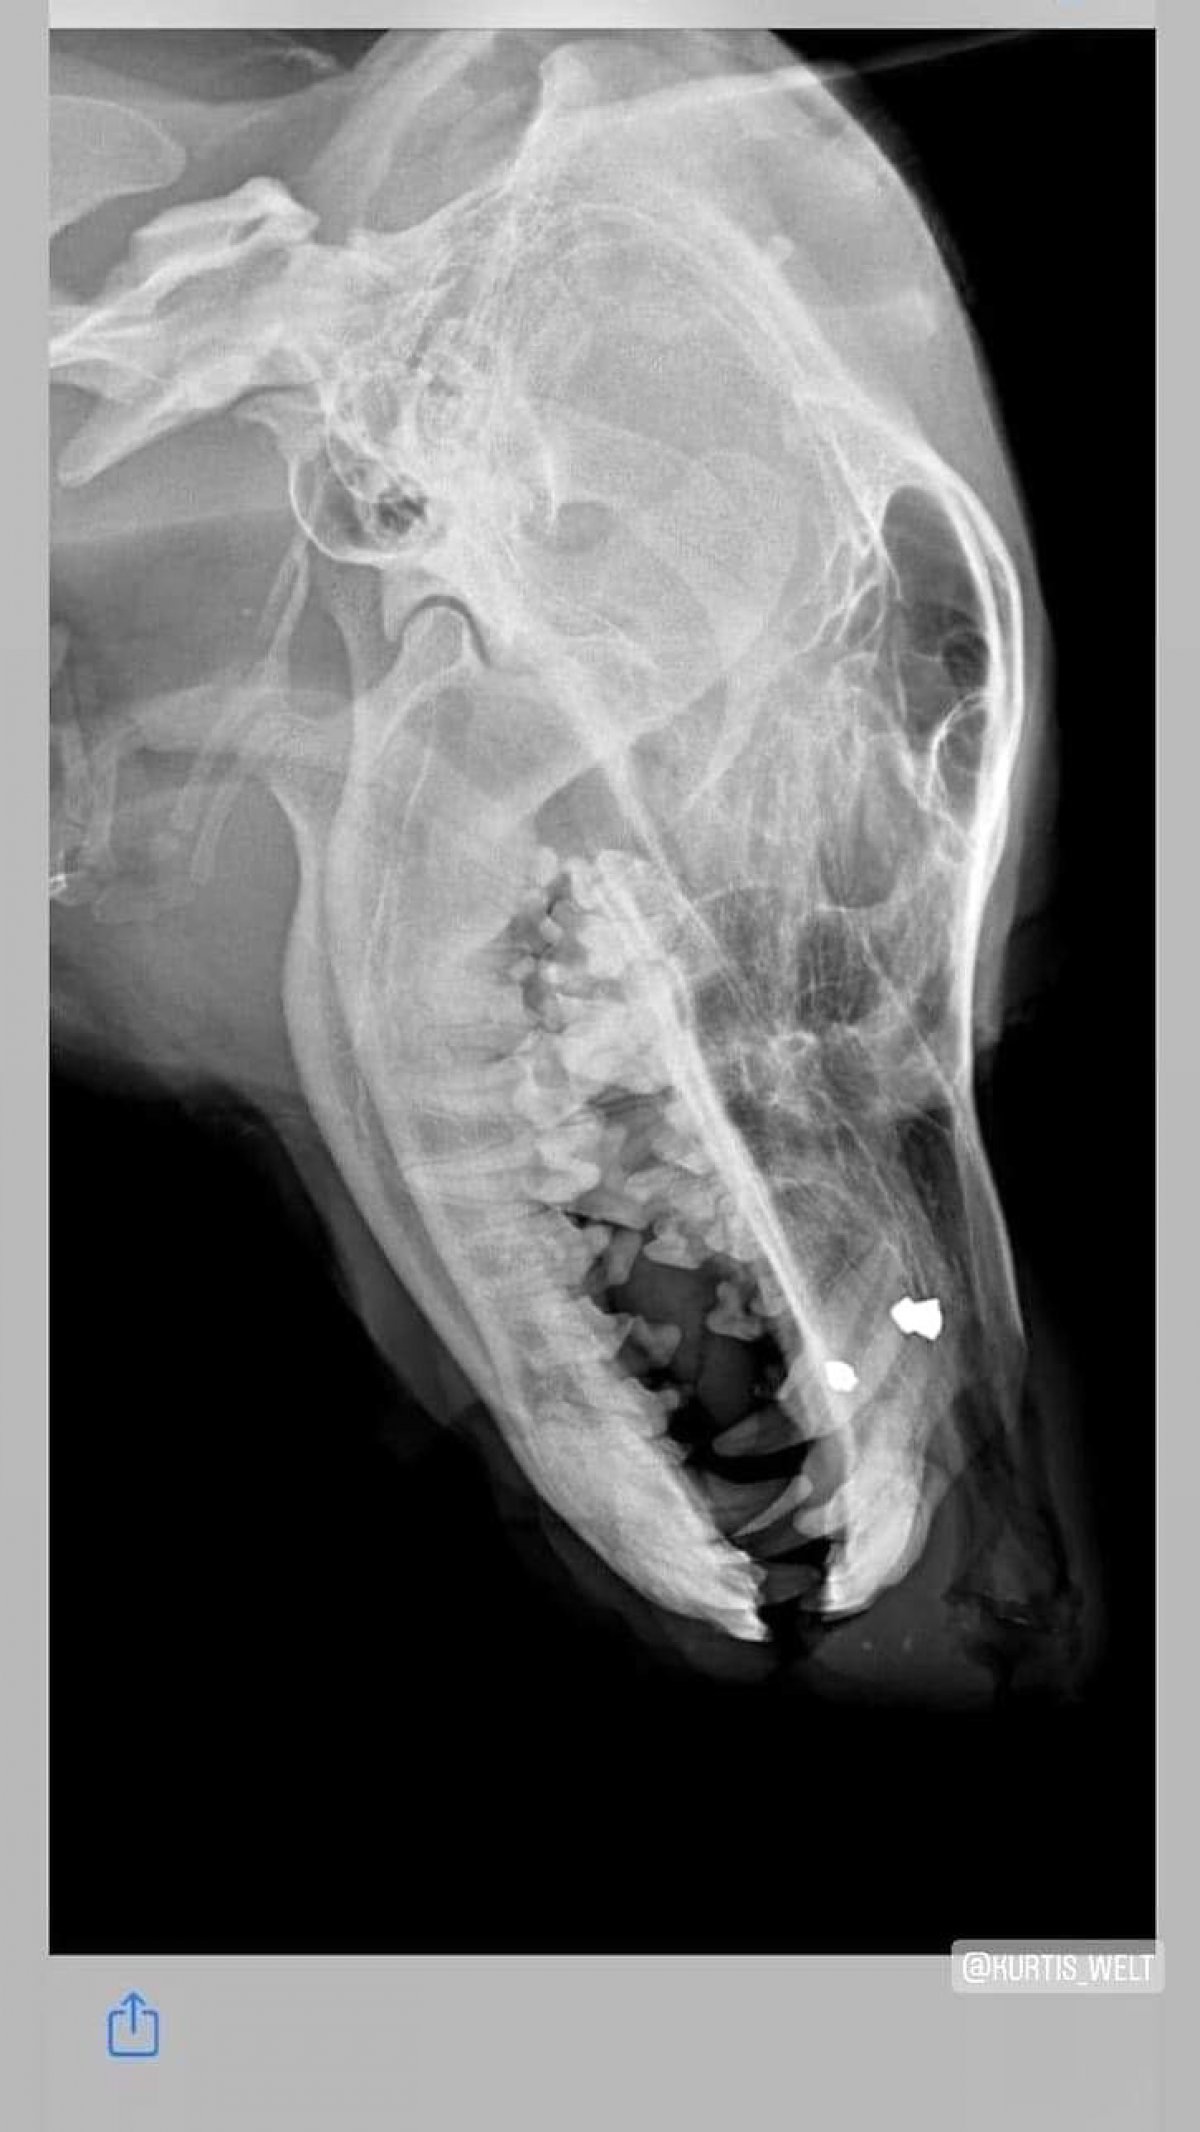

Erklärungen findet Ihr direkt in den Bildern, aber ACHTUNG, die Bilder zeigen Blut und Verletzungen!

Manchmal sagen Bilder mehr als Worte. Elli, ihre beiden Welpen und den Streuner "Rammstein" könnt ihr hier unterstüzen: